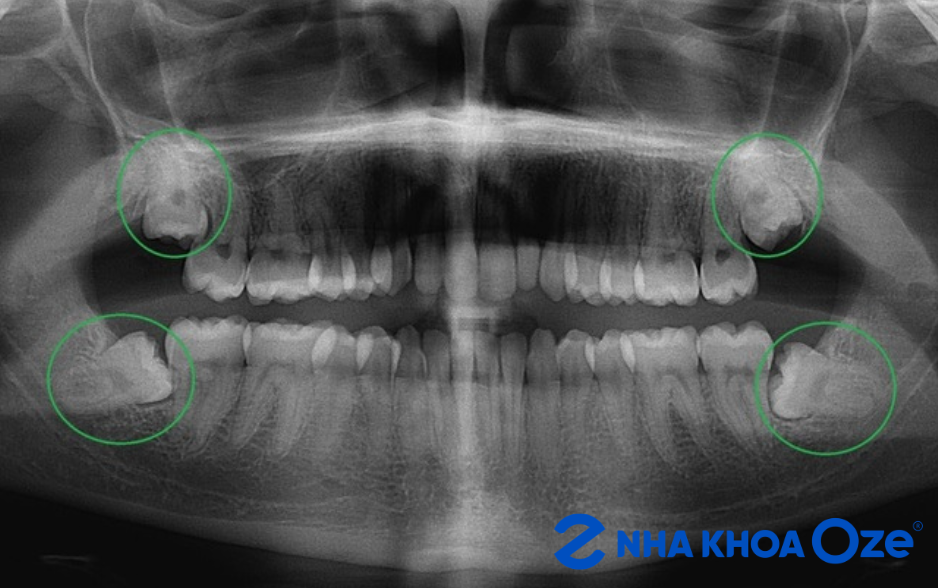

Trong các nhóm răng khôn, răng mọc lệch, mọc ngang hoặc mọc ngầm là nhóm khiến chi phí dễ chênh nhiều nhất. Lý do rất rõ: đây không còn là ca nhổ đơn giản mà thường là tiểu phẫu, đòi hỏi bác sĩ thao tác kỹ, đánh giá hướng mọc của răng và kiểm soát rủi ro tốt hơn.

Theo các bảng giá được công khai trên các kênh, nhóm răng mọc lệch nhẹ thường dao động khoảng 1.500.000–2.500.000 đồng/răng; răng mọc ngang, mọc ngầm hoặc lệch nhiều thường ở khoảng 2.000.000–5.000.000 đồng/răng; còn những ca phức tạp hơn có thể cao hơn tùy kỹ thuật, cơ sở điều trị và mức độ khó thực tế.